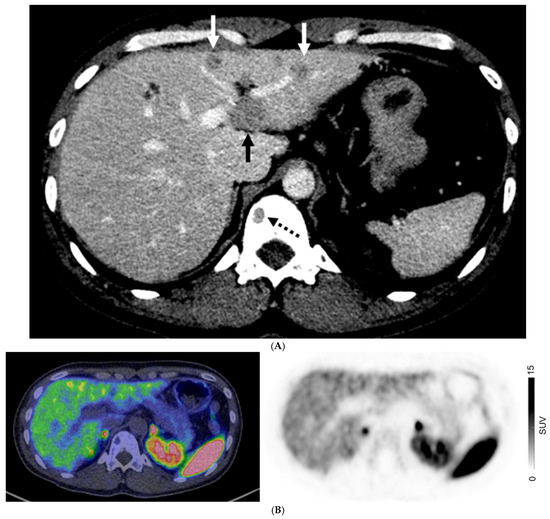

Figure 2.

A 67-year-old man with well-differentiated G1 small bowel NET, Ki 67 = 3% metastatic to liver. Staging CT showed mid-ileal tumor, regional nodal metastases, and bilobar liver metastases [CT stage: n1M1a]. 68Ga-DOTATATE PET/CT (A,B) Axial and Coronal—CT (left), fused PET/CT (middle) and PET (right); (C) Sagittal—Fused PET/CT (left) and PET (right) shows in addition, extrahepatic metastases including extraregional nodes including supraclavicular and cardiophrenic nodes (arrows in (A,C)), and peritoneal metastases (dotted arrows in (B,C)); overall, PET stage: n1M1c.

For patients with GEP NETs, no distant metastases (M0) were observed on both CI and PET in 186/369 (50.4%) of patients. There were 83 patients with GEP NETs who had discordant M-stage on CI and PET, in which PET suggested a higher stage in 75/83 patients (90.4%) and lower stage in 8/83 (9.6%) (Figure 2). For those with GEP NETs, extrahepatic metastatic disease was identified by PET in 42/114 (36.8%) patients where CI showed only liver metastases (M1a) (Figure 3).